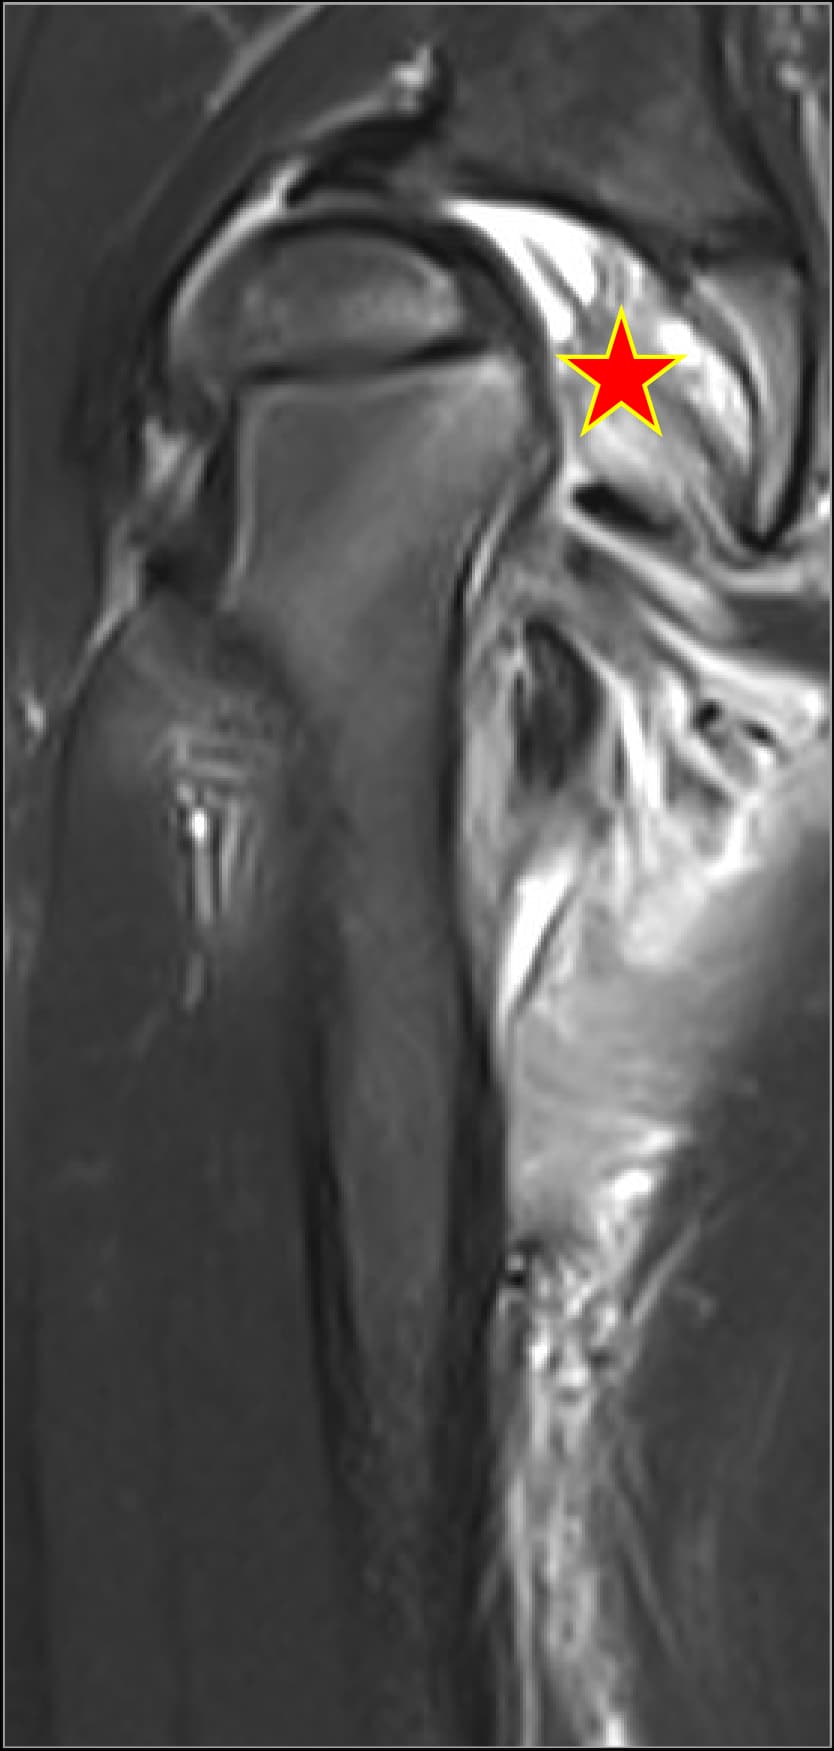

Hip & knee arthritisMRI case galleryClinical insights

Septic arthritis cases